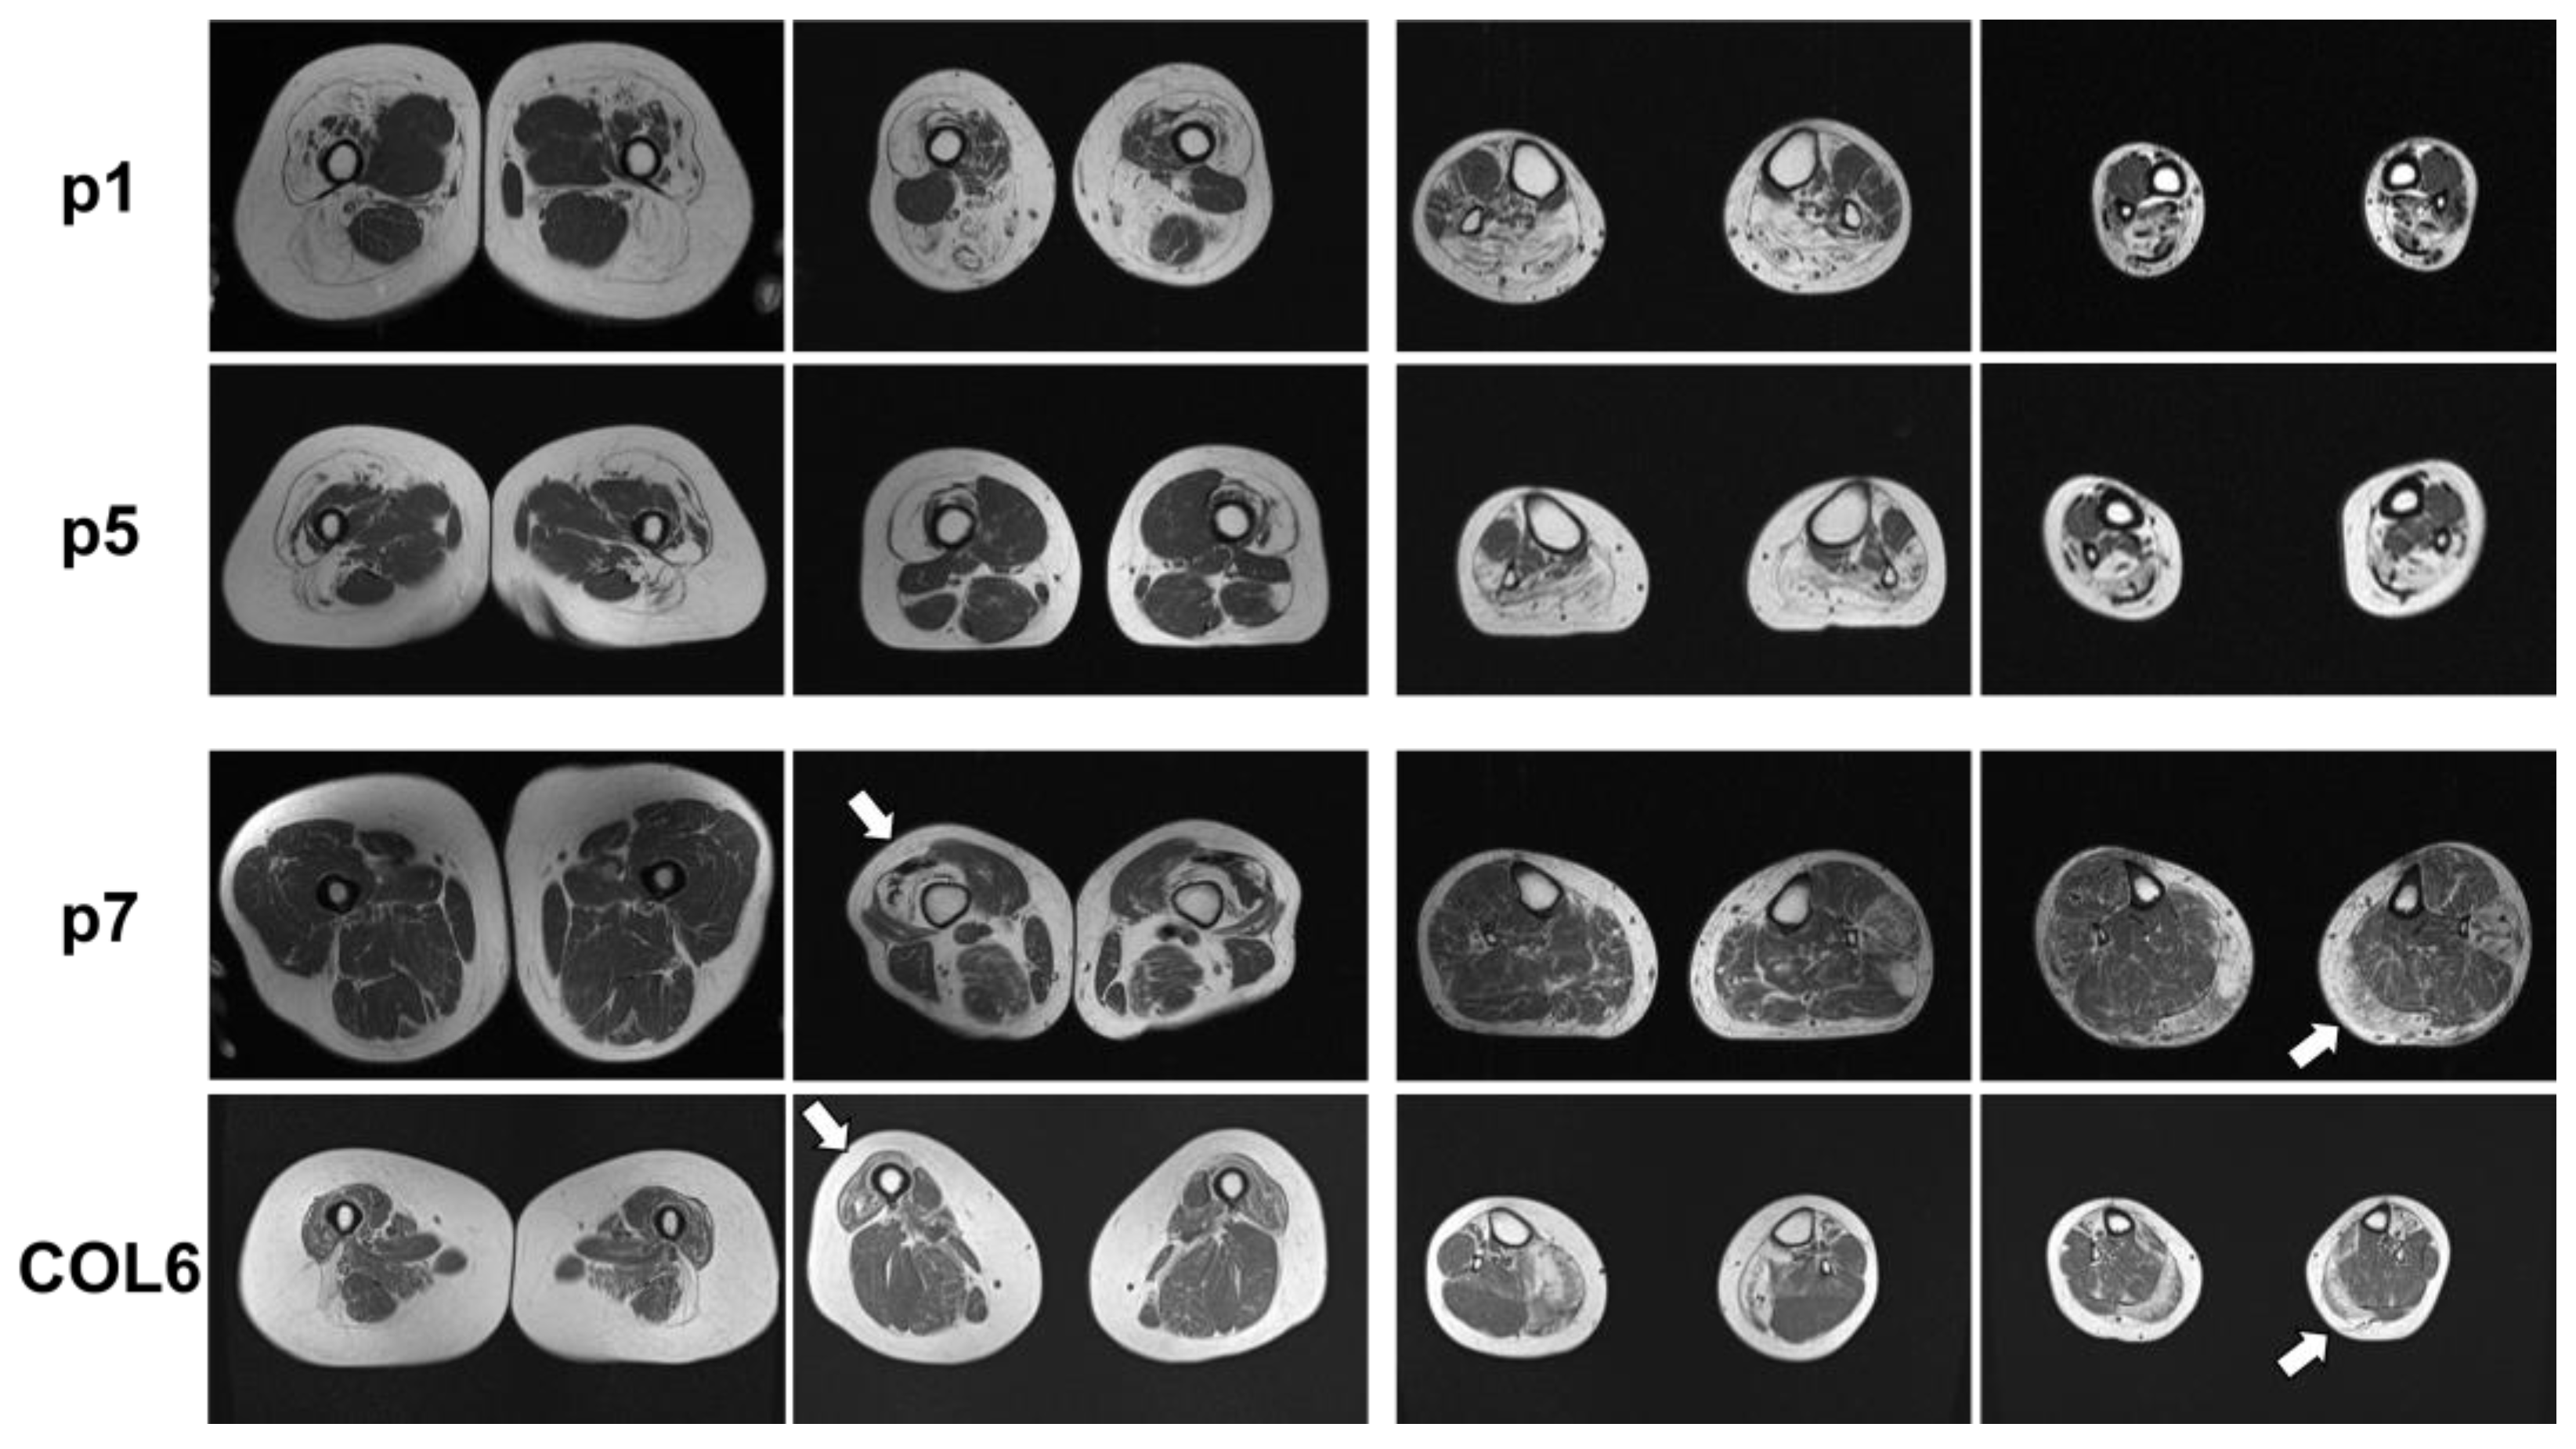

MRI of the leg muscles was performed on p1, p5, and p7; a data report is available on p2. Figure 2 shows severe fatty degeneration of the quadriceps muscles, semimembranosus, biceps femoris, and dorsal lower leg muscle changes in p1. To compare, the lower extremities of p5 had symmetrical, distally pronounced fatty involution of the quadriceps femoris, biceps femoris, caput longum, and thigh muscles as well as symmetrical fatty degeneration of the gastrocnemius, soleus, peroneus, and tibialis anterior in the calf muscles (Figure 2). There was no edema in the leg muscles. The adductor muscles and extensor digitorum longus muscles were spared from fatty degeneration (Figure 2). MRI data from p2 (not performed in our hospital) showed similar results with massive fatty degeneration of all leg muscles, sparing the adductor muscles.

Figure 2.

Muscle MRI of p1, p5, and p7 as well as a patient with a pathogenic COL6A1 mutation. p1: Muscle MRI of p1 with known BICD2-associated myopathy showed fatty degeneration of the thigh muscles, pronounced in the lateral biceps femoris muscles (left panels) and the calf muscles, pronounced in the soleus and gastrocnemius muscles (right panels). p5: Muscle MRI of p5 with novel BICD2 and FLNC variants showed fatty degeneration of the vastus lateralis and medialis muscles as well as the lateral biceps femoris muscle in the thigh (left panels) and fatty degeneration of the gastrocnemius and soleus muscles (right panels). p7: Muscle MRI of p7 with novel BICD2 and COL6A1 variants showed distal fatty degeneration of the thigh muscles (especially vastus lateralis (left panels, white arrow)) and asymmetric, left, and distally pronounced fatty degeneration in the gastrocnemius muscle, caput mediale, soleus, and peroneus longus muscles (right panels, white arrow). COL6: Muscle MRI of a patient with COL6A1-associated myopathy shows typical distal atrophy of vastus lateralis muscle (left panels, white arrow) and gastrocnemius muscles (right panels, white arrow). White arrows indicate muscle degeneration typically associated with COL6A1-associated myopathy.

MRI of the lower extremities of p7, who also carries a variant in the COL6A1 gene in addition to the variant in the BICD2 gene, displayed slightly asymmetric, distally pronounced fatty degeneration of the quadriceps femoris (arrows), biceps femoris, gastrocnemius, and left peroneus longus muscles (Figure 2). To compare, a patient with a genetically confirmed COL6A1-associated myopathy was included: note the pronounced degeneration and atrophy of the distal vastus lateralis and medial gastrocnemius muscles, which is similarly found in p7 (Figure 2, arrows).